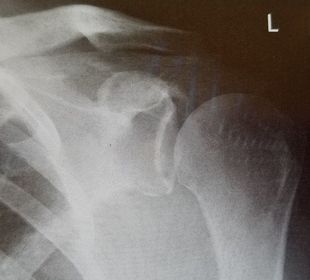

| AP Shoulder internal rotation | the MCP is tilted posteriorly as marked by the superior scapular angle is inferior to the clavicle |

| AP Shoulder | patient is rotated towards the unaffected shoulder: decreased thoracic superimposition over the scapular body |

| AP Shoulder | patient is rotated towards affected side:increased thoracic superimposition over the scapular body |

| Inferosuperior Axiolateral Shoulder | humerus is foreshortened - humeral head is distorted arm is not abducted 90 degrees from body |

| Grashey | Insufficient obliquity |

| Grashey | Excessive obliquity |

| Grashey | MCP is tilted posteriorly |

| AP Shoulder Neutral | ANATOMY: proximal humerus, lateral 2/3 of clavicle, open shoulder joint CRITERIA: humeral epicondyles are 45 degrees to the IR neither tubercle should be seen on the humeral head POSITIONING: CR perpendicular @ 1'' inferior to coracoid process |

| AP Shoulder Internal Rotation | CRITERIA: lesser tubercle in profile medially POSITIONING: CR perpendicular @ 1'' inferior to coracoid process |

| AP Shoulder External Rotation | CRITERIA: greater tubercle in profile laterally POSITIONING: CR perpendicular @ 1'' inferior to coracoid process |

| Scapular Y-Lateral | ANATOMY: humeral head resting in the 'Y' of the acromion and coracoid process CRITERIA: vertebral border and lateral border of scapula are directly superimposed humeral head is aligned with body of scapula POSITIONING: pt's unaffected arm is abducted 90 degrees, pt in 45-60 degree anterior oblique CR perpendicular @ scapulohumeral joint (neer) CR angled 10-15 degrees caudal @ scapulohumeral joint |

| Inferosuperior Axial Shoulder | ANATOMY: lateral view of the proximal humerus in relation to the glenoid fossa CRITERIA: lesser tubercle in profile medially humeral head is in the center of VOI POSITIONING: affected arm abducted 90 degrees, hand rotated externally with hand supinated CR horizontal 25-30 degrees medial to the scapulohumeral joint |

| Posterior Oblique Grashey | ANATOMY: glenoid cavity in profile glenohumeral joint center of VOI CRITERIA: open glenoid cavity anterior/posterior rims of glenoid cavity are superimposed POSITIONING: pt in 35-40 degree posterior oblique CR perpendicular @ glenoid cavity |